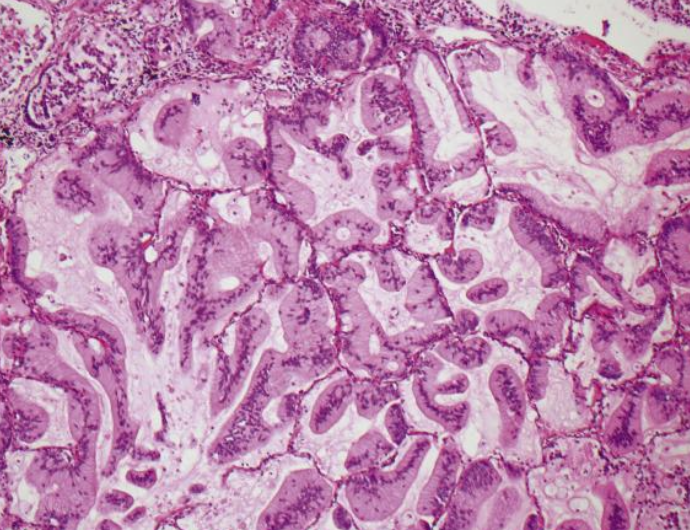

<p>Patrón de adenocarcinoma</p>

Patrón de adenocarcinoma

Patrón lepídico mucinoso

Lepídico, reviste la superficie de paredes alveolares, preservando arquitectura pulmonar